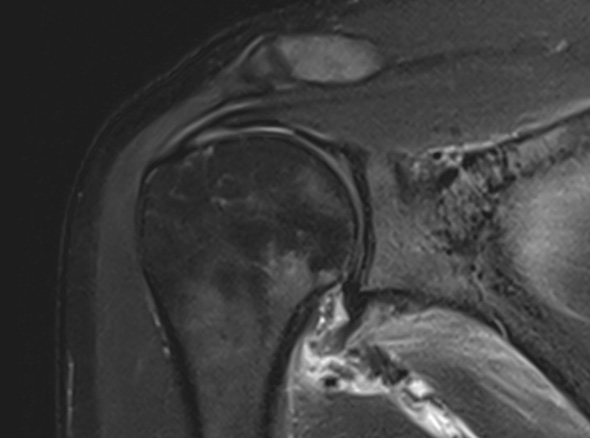

내시경을 통하여

유착된 관절낭을 유리화해 줍니다.

이러한 경우

내시경 시술을

고려합니다.

3-6개월 이상 보존적 치료를 하였으나 호전이 없는 경우

당뇨가 있는 경우

동반된 병변이 있는 경우 (석회, 충돌증후군, 회전근개 파열 등)

운동 범위의 감소가 매우 큰 경우